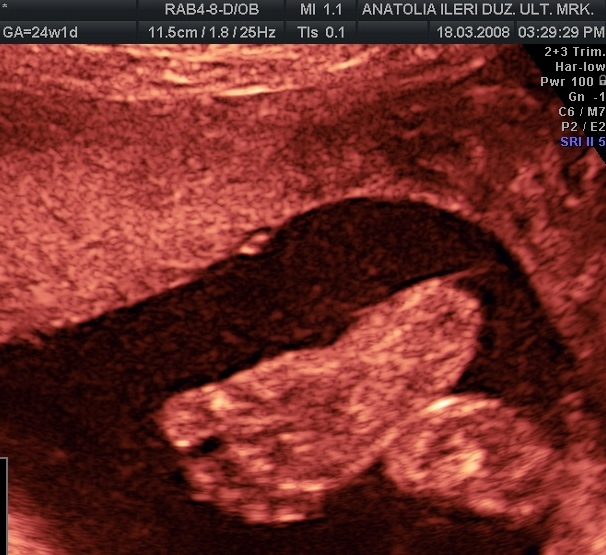

YÜZ PROFİL GÖRÜNTÜSÜ VE YUTKUNMA HAREKETİ

PARMAK EMME REFLEKSİ

OMURGANIN YAN PLANDA İNCELENMESİ

KULAĞIN GÖZLENMESİ

GÖĞÜS BOŞLUĞU VE KARIN İÇİ ORGANLARIN GÖZLENMESİ

DİZ VE AYAĞIN PROFİL GÖRÜNTÜSÜ

KAFA İÇİ (BEYİN) YAPILARININ DEĞERLENDİRMESİ